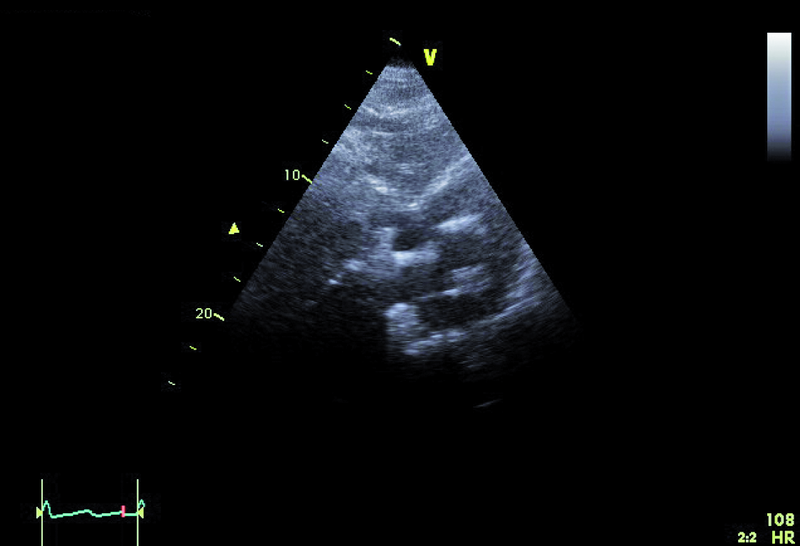

Powodem hospitalizacji 74-letniej kobiety był wielogodzinny ból w klatce piersiowej z towarzyszącą dusznością i niskim ciśnieniem tętniczym (90/60 mm Hg). W dniu hospitalizacji wystąpiło także krótkotrwałe omdlenie. W EKG zwracały uwagę cechy przebytego zawału serca ściany dolnej oraz brak progresji załamka R w odprowadzeniach V1-V4. Pacjentka od kilku lat chorowała na cukrzycę i nadciśnienie tętnicze. Po krótkotrwałym pobycie na oddziale szpitala rejonowego chorą przeniesiono do ośrodka referencyjnego. W wykonanej w trybie pilnym koronarografii uwidoczniono nieistotne zmiany miażdżycowe w naczyniach wieńcowych – maksymalnie do 40%. Wywiad, dziesięciokrotnie podwyższone stężenie d-dimeru i troponiny oraz powiększenie jamy prawej komory w badaniu echokardiograficznym stanowiły podstawę do poszukiwania zatorowości płucnej. Wykonane badanie TK klatki piersiowej pozwoliło uwidocznić skrzeplinę obejmującą pień oraz gałęzie płucne do poziomu tętnic segmentalnych. Ze względu na brak poprawy klinicznej w trakcie podawania heparyny zastosowano leczenie fibrynolityczne (alteplaza). Z powodu gorączki zastosowano także antybiotyk. W USG jamy brzusznej nie stwierdzono procesu nowotworowego, a badanie układu żylnego kończyn dolnych uwidoczniło skrzeplinę w żyle podkolanowej. Po kilku dniach od podania leku fibrynolitycznego obserwowano stopniowe ustępowanie duszności, stabilizację ciśnienia tętniczego, zmniejszenie parametrów zapalnych i stężenia d-dimeru. Rejestrowano także wzrost ciśnienia parcjalnego tlenu we krwi obwodowej. Dziesięć dni później wykonano kontrolne badanie echokardiograficzne (ryciny).

Dowodem klinicznym masywnej zatorowości płucnej był u chorej epizod omdlenia, utrzymująca się duszność, niskie ciśnienie tętnicze. Wiodącą rolę w rozpoznaniu choroby pełni tomografia komputerowa. Badanie echokardiograficzne uznawane jest za uzupełniające. Powiększenie jamy prawej komory stwierdzane w dniu hospitalizacji mówiło o możliwości istotnej dysfunkcji łożyska płucnego. Masywna zatorowość jest wskazaniem do włączenia leczenia fibrynolitycznego, zmniejszającego śmiertelność i zapobiegającego nawrotom choroby. Stan kliniczny pacjentki w wyniku zastosowanej alteplazy poprawił się. Rejestrowano zmniejszenie stężenia d-dimeru i troponiny. Czy jednak sytuacja chorej nie budzi już niepokoju? Mimo ograniczonej jakości przedstawionych rycin można dostrzec, że jama prawej komory jest przeciążona (ryc. 1, 2), a ciśnienie w łożysku tętnic płucnych szacowane z czasu akceleracji wypływu (66 ms!) jest podwyższone (ryc. 3). Im większa jest obstrukcja łożyska płucnego, tym więcej cech dysfunkcji prawej komory stwierdza się w badaniu ultradźwiękowym. Warunki obrazowania utrudniały odniesienie się do odcinkowej kurczliwości ściany wolnej i potwierdzenie lub wykluczenie objawu McConnella, czyli dysfunkcji segmentu środkowego. Ze względu na trudność w wizualizacji wsierdzia nie można było także ocenić zmiany pola powierzchni prawej komory (RV FAC). Mimo zachowanej funkcji kurczliwej prawej komory mierzonej wartością przemieszczenia pierścienia trójdzielnego (ryc. 4) uważny czytelnik z pewnością dostrzeże tkwiącą w prawej tętnicy płucnej skrzeplinę (ryc. 5, 6). Rzadko udaje się bezpośrednio uwidocznić skrzeplinę w łożysku tętnic płucnych. Kontrolne badanie TK klatki piersiowej potwierdziło obecność tzw. zatoru jeźdźca w pniu płucnym ze skrzeplinami w gałęzi prawej i gałęziach segmentalnych do płata dolnego prawego płuca. Obserwowano jedynie częściową regresję skrzeplin z tętnic płatowych i segmentalnych. Mamy więc do czynienia z nieskutecznością leczenia fibrynolitycznego (no clot resolution). Dobry stan kliniczny chorej nie wskazywał na potrzebę zastosowania leczenia chirurgicznego i embolektomii. Nie podjęto także decyzji o powtórnym leczeniu fibrynolitycznym z użyciem innego środka. Postanowiono kontynuować leczenie przeciwkrzepliwe i przeprowadzić po kilku tygodniach ponowną ocenę stanu klinicznego pacjentki i stanu łożyska tętnic płucnych. Wobec wieku chorej i licznych obciążeń internistycznych interesującą opcją leczenia (ale niestosowaną w tutejszym ośrodku) byłaby trombektomia za pomocą cewnika z miejscowym podaniem leczenia fibrynolitycznego.